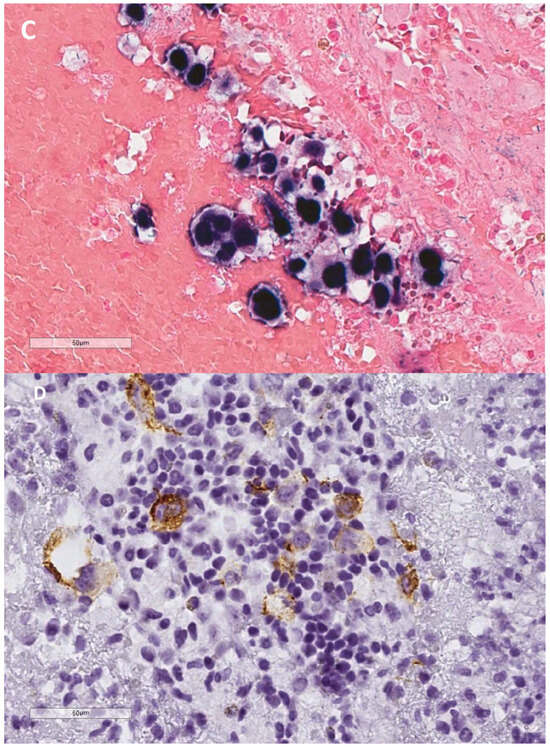

- Lajoie, V.; Lemieux, B.; Sawan, B.; Lichtensztejn, D.; Lichtensztejn, Z.; Wellinger, R.; Mai, S.; Knecht, H. LMP1 mediates multinuclearity through downregulation of shelterin proteins and formation of telomeric aggregates. Blood 2015, 125, 2101–2110. [Google Scholar] [CrossRef] [PubMed] [PubMed Central]

- Knecht, H.; Johnson, N.A.; Haliotis, T.; Lichtensztejn, D.; Mai, S. Disruption of direct 3D telomere-TRF2 interaction through two molecularly disparate mechanisms is a hallmark of primary Hodgkin and Reed-Sternberg cells. Lab. Investig. 2017, 97, 772–781. [Google Scholar] [CrossRef]

- Contu, F.; Rangel-Pozzo, A.; Trokajlo, P.; Wark, L.; Klewes, L.; Johnson, N.A.; Petrogiannis-Haliotis, T.; Gartner, J.G.; Garini, Y.; Vanni, R.; et al. Distinct 3D Structural Patterns of Lamin A/C Expression in Hodgkin and Reed-Sternberg Cells. Cancers 2018, 10, 286. [Google Scholar] [CrossRef]